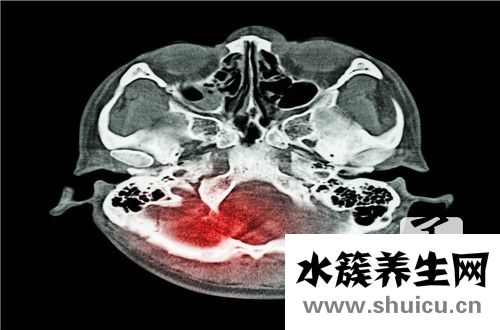

甲状腺钙化是甲状腺病确诊的关键指标值,当甲状腺结节出現增厚状况时,既能够造成甲状腺囊肿恶变肿瘤,还可以引起甲状腺囊肿良好病症,但相比于良好病症,恶变肿瘤产生增厚的可能性更大。因为肿瘤细胞迅速繁育,肿瘤中血管与化学纤维组织增生易出現钙质堆积造成包块增厚,除此之外肿瘤自身也会代谢一些物质例如糖蛋白、黏多糖等造成包块增厚。因而,甲状腺囊肿恶变肿瘤包块产生增厚的可能性十分大。

依据组织学特点,甲状腺病变中的增厚分成沙粒体、质间增厚和骨化。沙粒体是最受关心的增厚种类,存有于近50%的乳头状癌中,而罕见于别的型甲状腺癌,甲状腺囊肿良好变病中也是极其少见。沙粒体是一种直徑为50~70μm的内切圆分片层的构造,状如散砂,横切面呈圆葱样,多与肿瘤体细胞伴行,多见于乳头化学纤维枢轴、化学纤维性质间和实性肿瘤体细胞巢中间。

质间增厚形状多种多样,可主要表现为标准或不规律的颗粒、团小块、环形、弧状或条状,骨化是在质间增厚的基本上产生的,二者在影象上没法辨别,其组织学成份与一切正常骨类似。环状增厚是质间增厚的典型性主要表现。